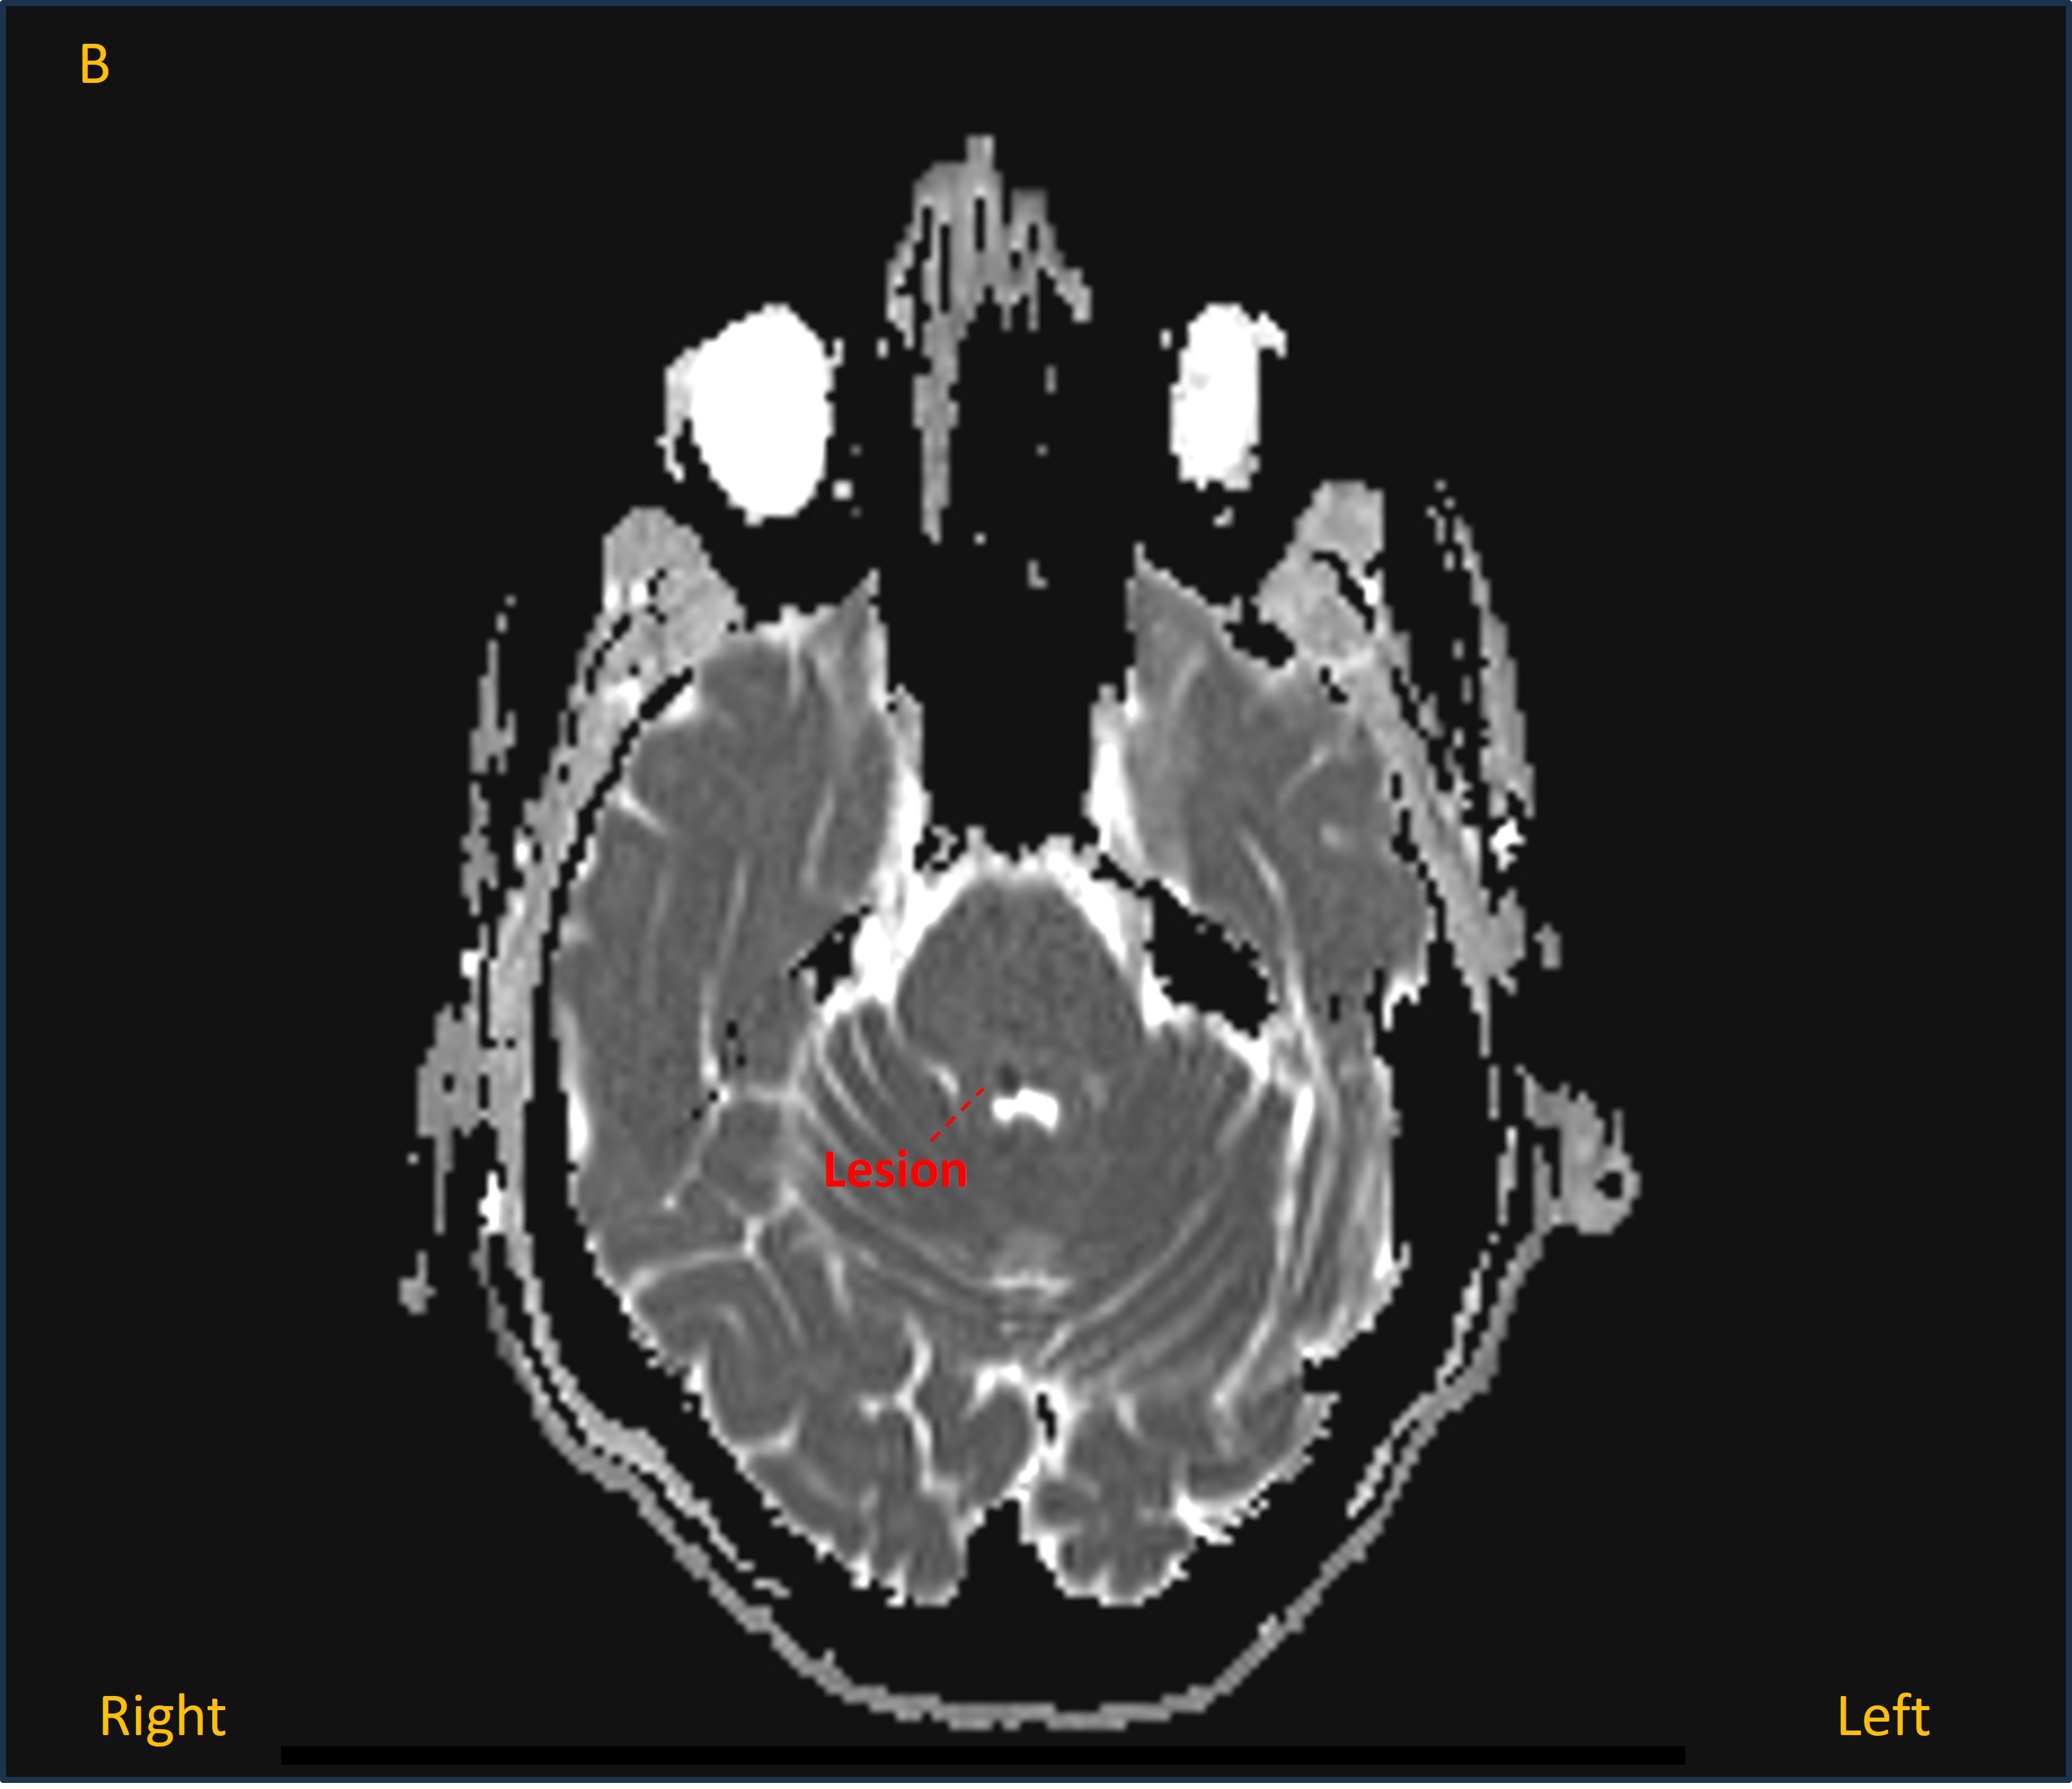

A CT head was unremarkable, but has low sensitivity for many lesions in the posterior fossa, so an MRI was performed. This showed an acute lacunar infarction in the right dorsal upper pontine tegmentum - bright on diffusion-weighted imaging (image A) and dark on apparent diffusion coefficient map (image B).

MRI A